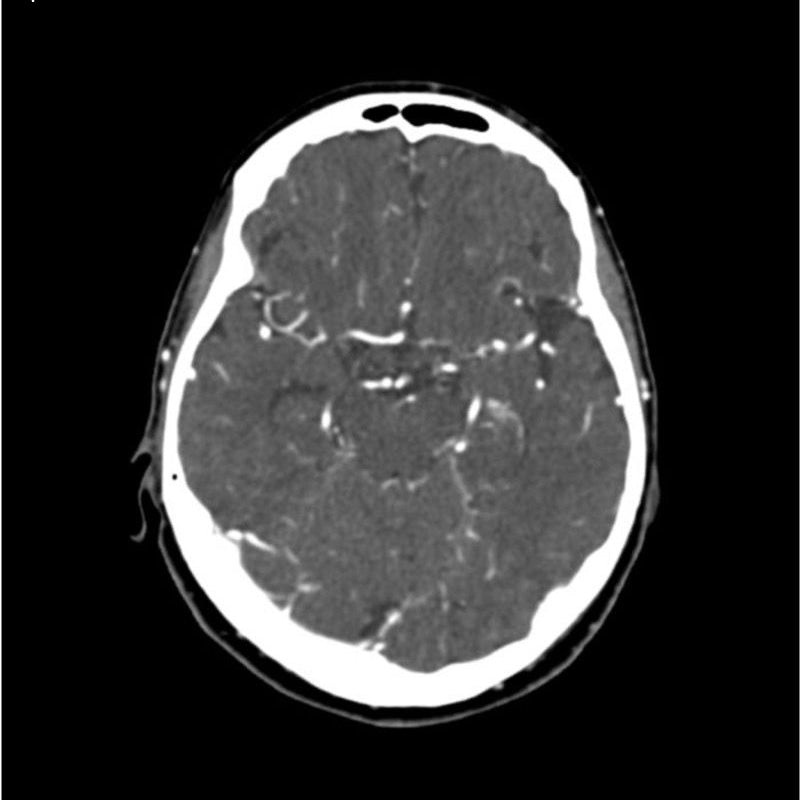

CTA Head and Neck Phantom for CT Scan and X-Ray Training

This phantom simulates a contrast medium enhanced head in arterial phase (CT angiography). The neck and upper thorax are included up to the aortic arch and the fifth thoracic vertebra. The vertex is included until approximately 0.5 cm below skin level. The thoracic phantom section excludes shoulder and back parts that are typically not part of CTA examinations. The interncal carotid artery has calcifications on both sides with moderate stenosis on the right side. Otherwise, the phantom has no significant vascular pathologies.

The phantom can be used in CT (including CBCT) to evaluate and optimize CTA imaging performance and post-processing applications such as vessel segmentation, including AI-enabled applications. It is also nicely suited for training purposes. The phantom provides a detailed and realistic simulation of vascular structures, soft and bone tissue, including small details such as lymph nodes. Air voids are filled with a cellulose-polymer composite of approx. -160 HU.

Realistic simulation of head and neck vessels up to the aortic arch, bone and soft tissues.

Calcifications of the internal carotid artery at the carotid bifurcation on both sides with mild stenosis on the right side.